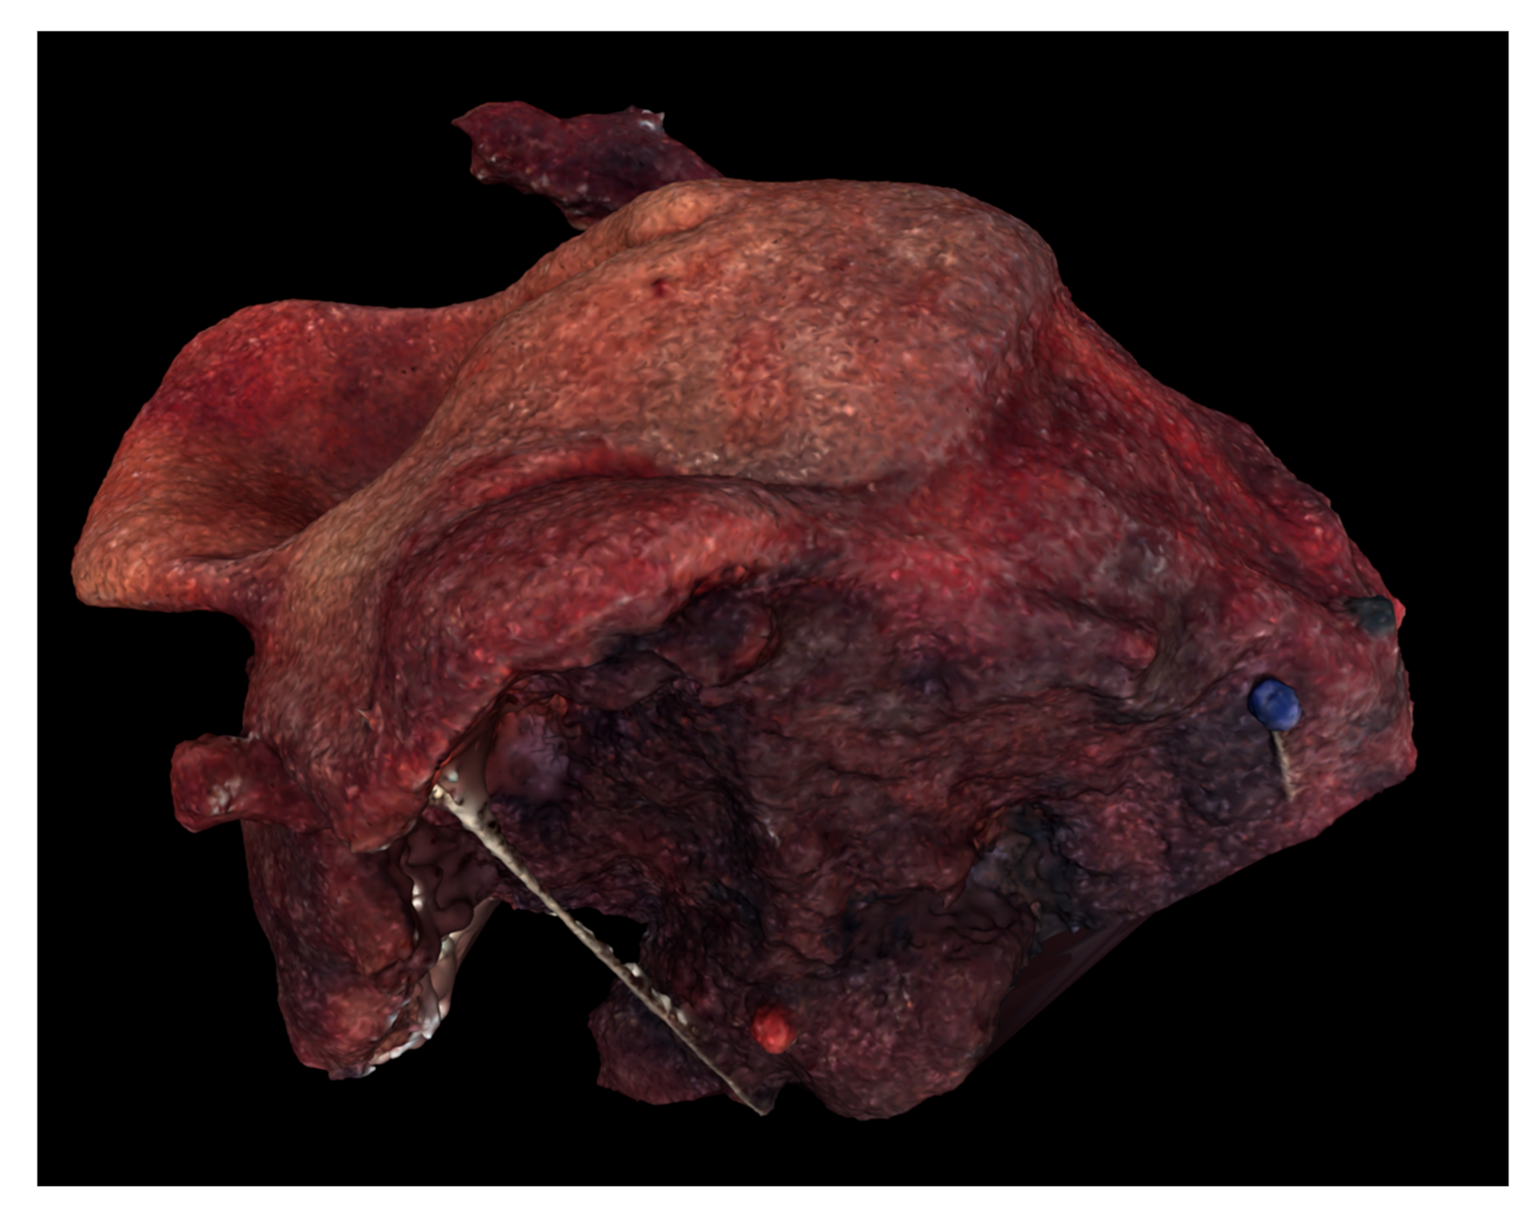

Table 1 summarizes the main parameters from the reconstruction. “Photographs taken” refers to the number of smartphone photographs, taken from various orientations, introduced into the photogrammetry software. Aligned photographs were able to be utilized during the computation and construction of the digital 3D model (Figure 4, Figure 5 and Figure 6). Processing time gives an approximate total time span required by the alignment, dense cloud creation, and meshing steps.

Figure 6.

Digital 3D model of Case 3 using Meshlab.

Digital and physical models of the surgical resection block were produced within one week of the operation. The 3D model dimensions were scaled up from the true dimensions of the resection block due to the small size of each tumor. Enlarging the dimensions of the model allowed for improved visualization of surface topography and anatomical details. For Case 1, the model produced by binder jetting conveyed more information than the material extrusion model because of the added color texture made possible by binder jetting (Figure 7 and Figure 8). Using material extrusion, the model was made of simple ABS-like white polymer with less detail.

Production time for printing of the 3D model ranged from two to nine hours and printing costs ranged from 25 to 140 EUR: 24.90 EUR/28.41 USD (Case 1), 38.20 EUR/43.59 USD (Case 2) and 141.00 EUR/160.89 USD (Case 3).